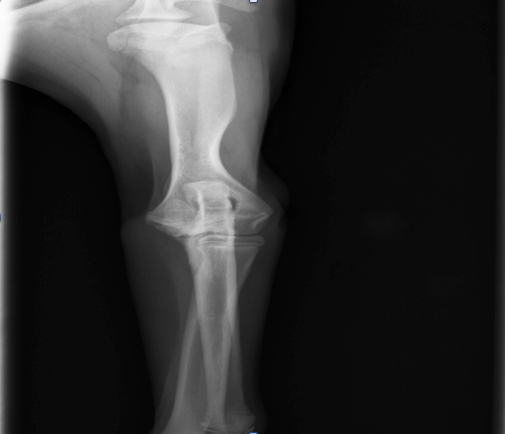

Aaron war munter und aufmerksam, sein Herz-Kreislauf-System und die Palpation des Abdomens waren unauffällig. Seine innere Körpertemperatur lag mit 38,9°C im physiologischen Bereich. Er ging hochgradig lahm auf der linken Vordergliedmaße. Bei der Palpation des linken Vorderbeines konnte man eine deutliche Gelenkfüllung und eine Schmerzhaftigkeit des Ellbogengelenks feststellen. Alle anderen Gelenke waren frei beweglich und nicht schmerzhaft. Es wurde eine Röntgenuntersuchung beider Ellenbögen und Schultern durchgeführt. Die Schultern stellten sich röntgenologisch völlig unauffällig dar. An beiden Ellenbögen konnten Veränderungen in Form einer  Osteochondrosis dissecans (OCD = Knorpelveränderung) nachgewiesen werden, und der linke Ellbogen war hochgradig verdächtig für eine Ellbogendysplasie (ED) mit einem Frakturierten Processus Coronoideus medialis (FCP= abgebrochenes Knochenteil). Aufgrund der röntgenologischen Befunde wurden beide Ellenbögen arthroskopiert. Der Verdacht einer Ellbogendysplasie konnte in der Arthroskopie bestätigt werden. Das abgebrochene Knochenteil wurde entfernt und die Knorpelschuppen der OCD beidseits abgetragen.

Osteophytäre Zubildungen (Arthrosen) wurden am Gelenk diagnostiziert

In den nächsten Tagen erhielt der Hund ein Schmerzmittel und Hyaluronsäure zum Knorpelaufbau und ging regelmäßig zur Physiotherapie. Aaron lief vier Wochen lahmfrei ohne Schmerzmittel. Danach ging er wieder zunehmend lahm. Er zeigte wieder deutliche Gelenkergüsse in beiden Ellenbögen. Es wurde eine Computertomographie-Untersuchung (CT) beider Ellenbögen durchgeführt. Im CT wurden mehrere osteophytäre Zubildungen (Arthrosen) am Gelenk diagnostiziert, welche infolge des permanenten Entzündungsreizes entstanden sind. Weitere knöcherne Veränderungen und eine erneute abgelöste Knorpelschuppe (OCD) konnte nicht gefunden werden.